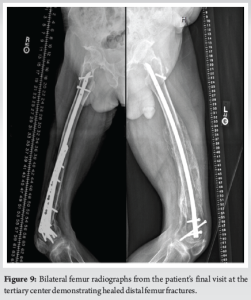

During the patient’s next follow-up visit, 1 month later, the patient complained of palpable hardware around his right knee. Repeat radiographs revealed a hypertrophic non-union with proximal migration of the nail and loosening of the distal interlocking screws (Fig. 5). He was initially treated conservatively; however, symptoms persisted for over 2 months. He then underwent removal of the right distal interlocking screws, augmentation with plate and screw fixation, and revision of the proximal interlocking screws. In a subsequent follow-up 3 weeks later, the patient noted a palpable mass around his left distal thigh. In addition, he developed a sacral decubitus ulcer that required referral to outpatient wound care. Conservative treatment with repeat imaging in 2 months was planned; however, the patient was lost to follow-up. The patient presented to the clinic 1 year later with complaints of palpable distal thigh masses bilaterally and feelings of heaviness in his legs. Radiographs revealed bilateral fracture healing with heterotopic ossification on the left, a well-fixed distal femur plate on the right, and no hardware failure (Fig. 6 and 7). The prominent left-sided heterotopic ossification and palpable right-sided distal femur plate caused significant discomfort. These complications greatly decreased his quality of life and caused him extreme distress. He was referred to a tertiary center for a second opinion, where radiographs revealed bilaterally healed distal femur fractures (Fig. 8 and 9). Removal of the right distal femur plate, left intramedullary nail, and left TTC nail was recommended to improve his quality of life. Unfortunately, the patient passed away from causes indirectly related to his orthopedic injuries before any further follow-up or surgical interventions could take place.